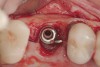

When dental implants fracture, they typically require removal. Implant fracture can lead to abutment instability and screw loosening, which may result in inflammation and infection as subgingival bacteria colonize normally inaccessible regions. This can lead to marginal and buccal/facial bone loss associated with the location of the fracture. When the coronal aspect of a restored implant fractures, it can cause mobility of the abutment and cemented restoration (Figure 1). In addition, multiple try-ins of ill-fitting restorations and torqueing of abutment screws can fracture an implant (Figure 2). Bone loss, swelling, and discomfort persisted after localized debridement and systemic antibiotic therapy; therefore, this implant was eventually removed.

(2.) The implant is fractured, and significant bone loss is evident. This implant required removal and site augmentation to facilitate new implant placement.

Figure 2